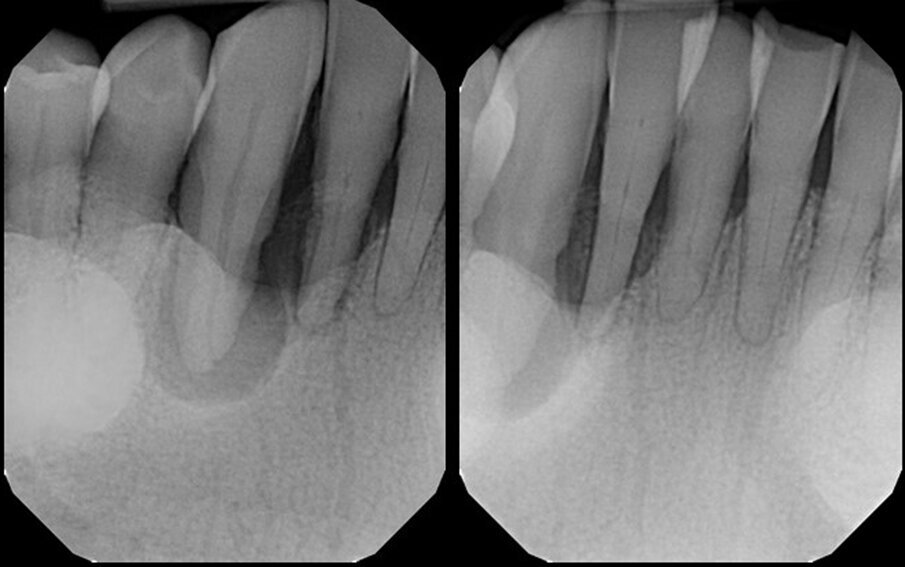

Periapical radiographs were taken to access the conditions present (Figs. 1a & b). A large area of bone loss was noted around the entire root of the canine, which had no osseous support. The lateral incisor presented with 90% bone loss and the central incisor 75% bone loss. The patient was informed that, owing to the amount of bone loss, extraction of the three teeth was the recommended treatment that could be performed on those teeth.

Figs. 1a & b: Pretreatment radiograph demonstrating signicant bone loss associated with the mandibular right central incisor, lateral incisor and canine.